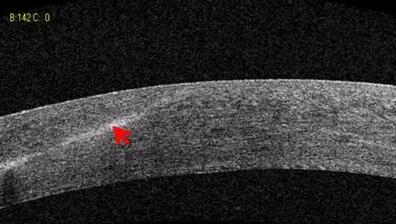

1、角膜分层观察 OCT 轴向分辨率高达5μm,远高于UBM(20--60μm),可识别出泪膜、上皮层、前弹力层、基质层、后弹力层/内皮层

2、角膜厚度评估,角膜水肿、瘢痕、混浊、溃疡、异物、炎症、胬肉等断层观察

3、角膜屈光手术后角膜瓣观察、角膜厚度评估等

4、后弹力层角膜内皮移植术(DSEK)、板层角膜移植术、白内障术后内皮层脱落等术后观察